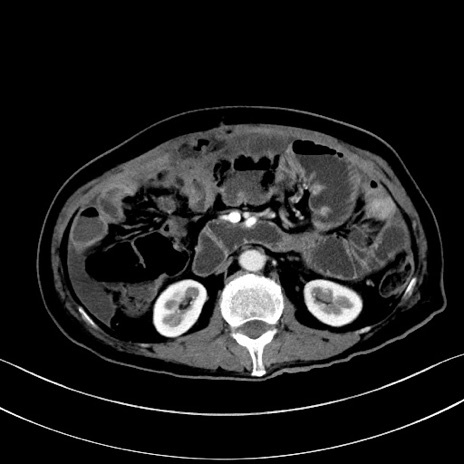

冠状断像

【症例】60歳代男性

【主訴】嘔吐

【現病歴】胃癌にて胃全摘後。食思不振が悪化し、夜中に嘔吐することがある。

【既往歴】胃癌、胃全摘、脾摘、胆摘後

【データ】WBC 5900、CRP 10.56